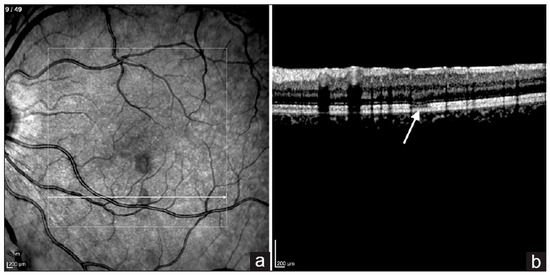

- Agarwal, A.; Aggarwal, K.; Dogra, M.; Kumar, A.; Akella, M.; Katoch, D.; Bansal, R.; Singh, R.; Gupta, V. Dengue-Induced Inflammatory, Ischemic Foveolitis and Outer Maculopathy: A Swept-Source Imaging Evaluation. Ophthalmol. Retin. 2019, 3, 170–177. [Google Scholar] [CrossRef]

- Teoh, S.C.; Chee, C.K.; Laude, A.; Goh, K.Y.; Barkham, T.; Ang, B.S.; Eye Institute Dengue-related Ophthalmic Complications Workgroup. Optical Coherence Tomography Patterns as Predictors of Visual Outcome in Dengue-Related Maculopathy. Retina 2010, 30, 390. [Google Scholar] [CrossRef]

- Akanda, M.; Gangaputra, S.; Kodati, S.; Melamud, A.; Sen, H.N. Multimodal Imaging in Dengue-Fever-Associated Maculopathy. Ocul. Immunol. Inflamm. 2018, 26, 671–676. [Google Scholar] [CrossRef] [PubMed]

- Mahendradas, P.; Acharya, I.; Rana, V.; Bansal, R.; Ben Amor, H.; Khairallah, M. Optical Coherence Tomography and Optical Coherence Tomography Angiography in Neglected Diseases. Ocul. Immunol. Inflamm. 2024, 32, 1427–1434. [Google Scholar] [CrossRef] [PubMed]

- Aggarwal, K.; Agarwal, A.; Katoch, D.; Sharma, M.; Gupta, V. Optical Coherence Tomography Angiography Features of Acute Macular Neuroretinopathy in Dengue Fever. Indian J. Ophthalmol. 2017, 65, 1235. [Google Scholar] [CrossRef]